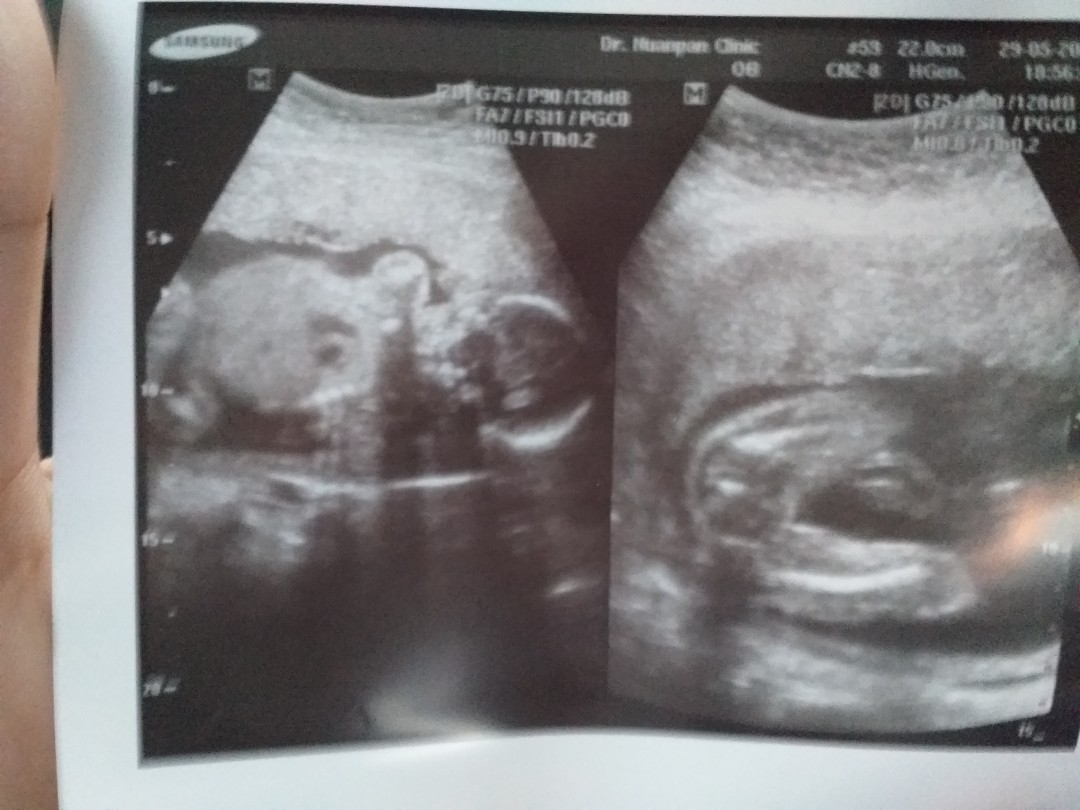

ขอดู รูปซาว หน่อยค่ะว่าเหมื่อนกันไหม หมอ บอกว่า เป็น ญ เพราะไม่มีจู๋โผลมา บ้านอื่น ได้ ญ แบบนี้หรือเปล่าค่ะ แม่แอบกังวล อยากได้ญ กลัว จู่ โผล่มาทีหลัง 😁23+4.

ลูกสาวเหมือนกันจ้า

ไม่มีจู๋เหมือนกันจ้า